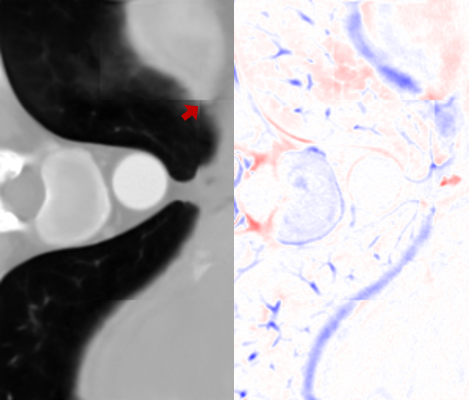

where Igtx=Ix(y,z)subscriptsuperscript𝐼𝑥𝑔𝑡superscript𝐼𝑥𝑦𝑧I^{x}_{gt}=I^{x}(y,z) and Igty=Iy(x,z)subscriptsuperscript𝐼𝑦𝑔𝑡superscript𝐼𝑦𝑥𝑧I^{y}_{gt}=I^{y}(x,z) in the densely-sampled volume I𝐼I. From the axial perspective, Isag(x,y,z)subscript𝐼𝑠𝑎𝑔𝑥𝑦𝑧I_{sag}(x,y,z) and Icor(x,y,z)subscript𝐼𝑐𝑜𝑟𝑥𝑦𝑧I_{cor}(x,y,z) provide line-by-line estimations for the missing axial slices. However, since no constraint is enforced on the estimated axial slices, inconsistent interpolations lead to noticeable artifacts, as shown in Fig. 4. We resolve this problem in the RFN stage of the proposed pipeline.

Refer to caption

(a) Isagz(x,y)superscriptsubscript𝐼𝑠𝑎𝑔𝑧𝑥𝑦I_{sag}^{z}(x,y)

(b) Icorz(x,y)superscriptsubscript𝐼𝑐𝑜𝑟𝑧𝑥𝑦I_{cor}^{z}(x,y)

(c) Iavgz(x,y)superscriptsubscript𝐼𝑎𝑣𝑔𝑧𝑥𝑦I_{avg}^{z}(x,y)

(d) Ifuse(x,y)subscript𝐼𝑓𝑢𝑠𝑒𝑥𝑦I_{fuse}(x,y)

Figure 4: (a) The axial slice generated from Isagsubscript𝐼𝑠𝑎𝑔I_{sag}. (b) The axial slice generated from Icorsubscript𝐼𝑐𝑜𝑟I_{cor}. Some details are better resolved by (a) and others by (b). Both of them exhibit directional artifact due to a lack of constraints in the (x,y) plane. This is resolved through RFN in (d), which refines their average Iavgsubscript𝐼𝑎𝑣𝑔I_{avg}, as shown in (c)